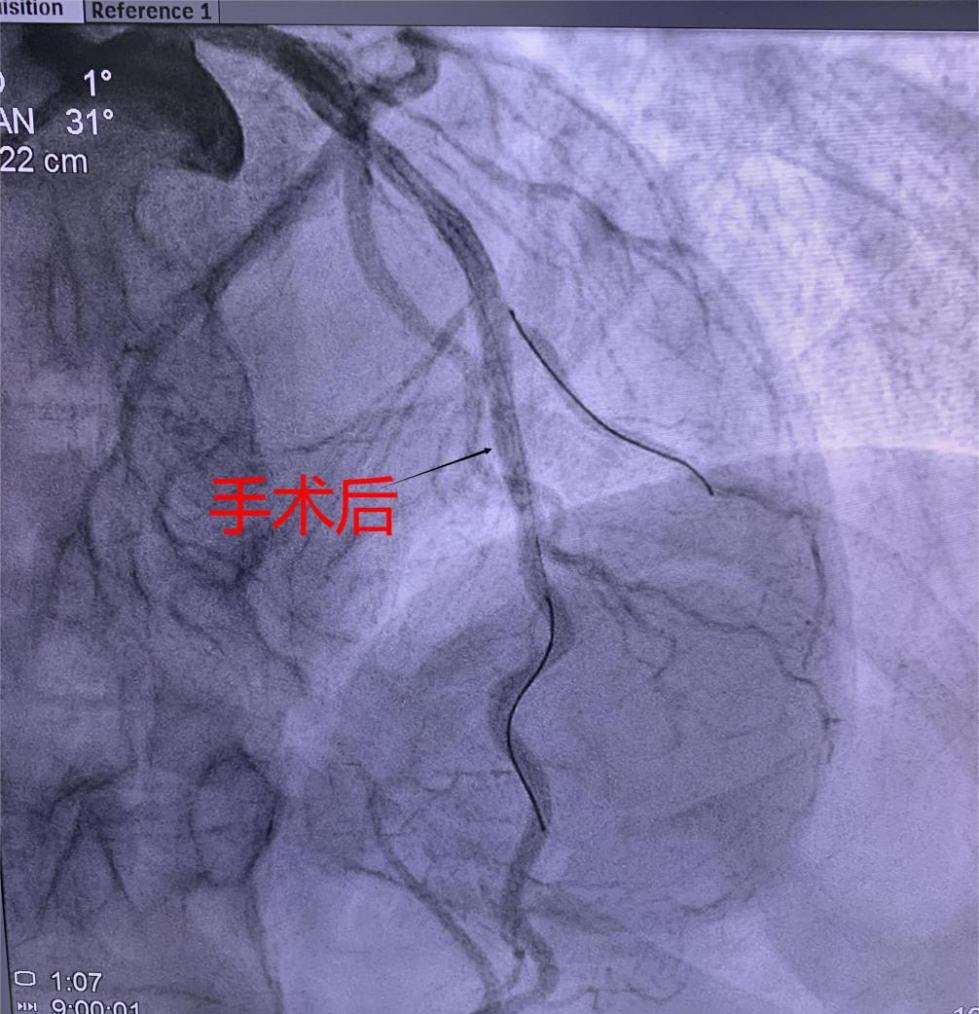

支架植入術前經過充分預擴張,按照規范的可吸收支架操作流程,快速送入可吸收支架到靶血管病變部位,精準定位后14個大氣壓釋放,生物可吸收支架后擴球囊選擇不超過支架直徑0.25mm的非順應球囊擴張。充分球囊后擴張,以保證支架貼壁良好,血流速度加快,造影完美,手術順利結束。

(可吸收支架植入手術中)及(手術造影圖)